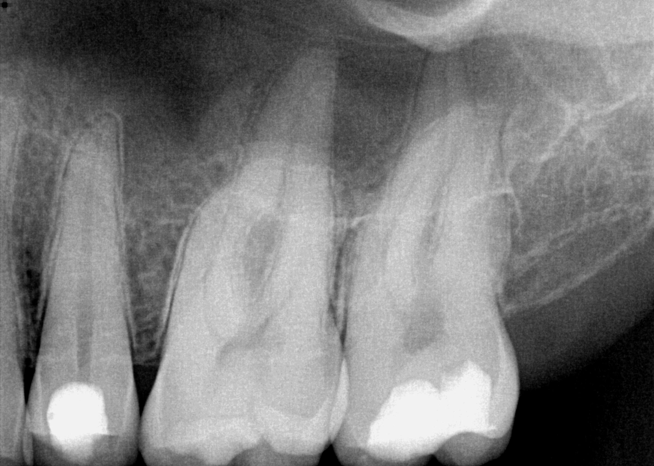

Fig 3. Preoperative maxillary left bicuspid.

Figure 3

Case Two: Maxillary Left Second Bicuspid (No. 13)

The patient presented with temperature sensitivity and pain during mastication (Figure 3). Local anesthesia was delivered, and steps 1 through 4 were performed.